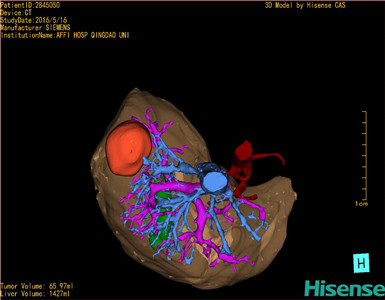

将0.625mm双源薄层CT资料的静脉期和动脉期Dicom格式文件导入海信CAS系统。

通过调节窗宽窗位调整CT序号,对肿瘤,肝实质,胆囊,下腔静脉,肿瘤,肝动脉、门静脉及肝静脉等进行三维重建;系统自动计算肿瘤体积和肝脏体积。

模拟手术操作,自动计算切除肿瘤体积。肝脏体积为1427ml,肿瘤体积为65.97ml,肿瘤体积为肝脏体积的4.6%,通过比对40-50岁正常肝脏体积为1368.38±279.24ml,通过术前模拟手术,精准判断切除后剩余肝脏体积能耐受,避免肝衰竭发生。

术前三维重建:

重建图片